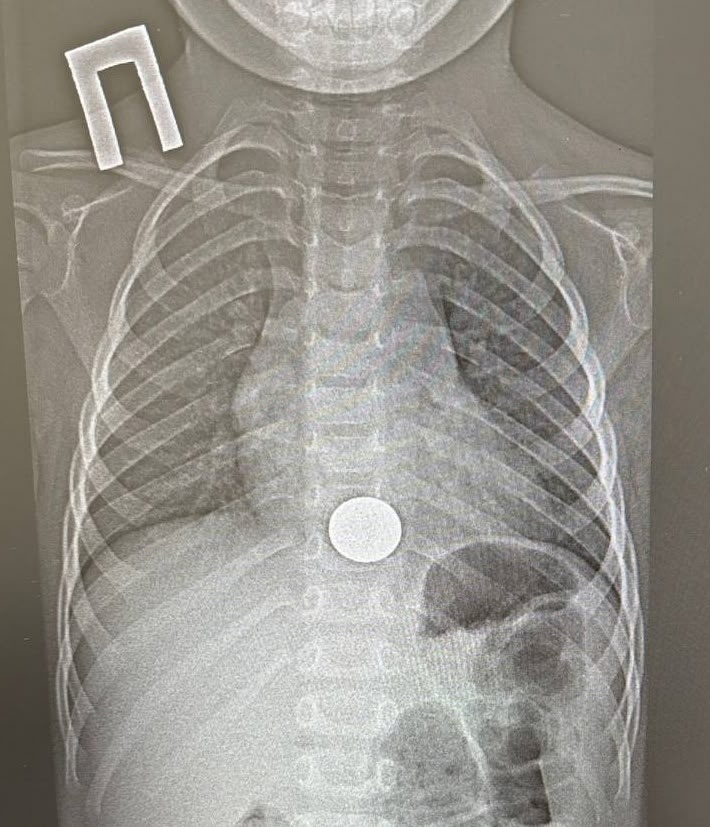

Татарстанские врачи спасли ребенка, который проглотил монету

В Нижнекамскую детскую районную больницу срочно доставили трёхлетнего малыша, который случайно проглотил монету. Хирург-эндоскопист Игорь Шогоров провёл малотравматичную операцию и извлёк инородное тело из пищевода. Это заняло всего минуту. Уже на следующий день ребёнка выписали домой в удовлетворительном состоянии, сообщили в Минздраве Татарстана.

Медики советуют родителям тщательнее следить за детьми. Мелкие предметы, например, монеты, батарейки, магниты, стоит держать в труднодоступном месте.